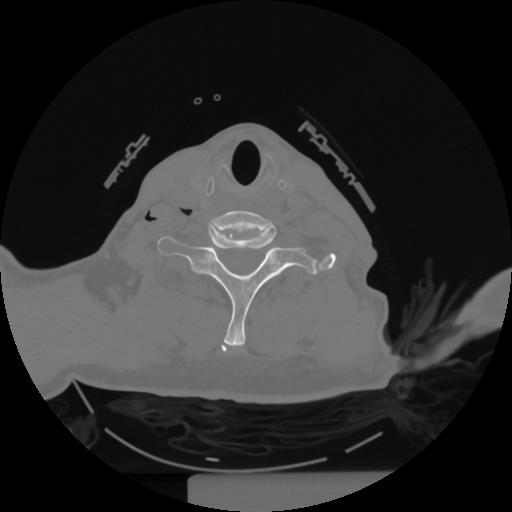

12 P.BLANDAS,,Vol,0.5,P.BLANDAS,,